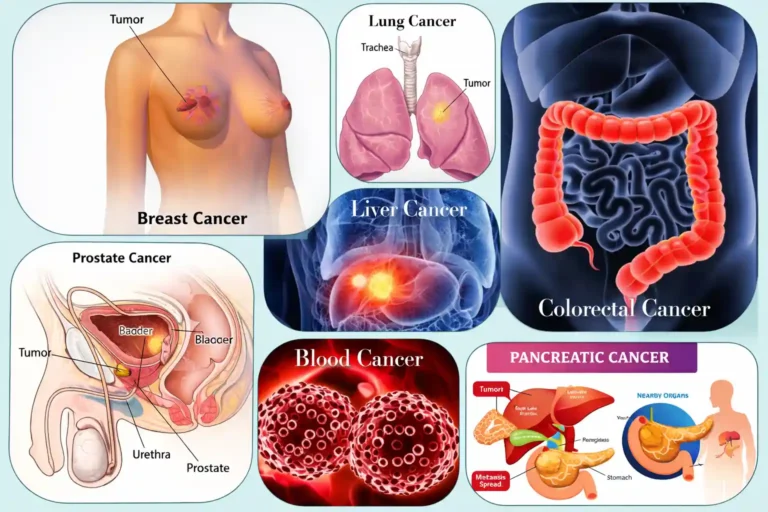

ROLE OF STEM CELL THERAPY

IN DIFFERENT TYPES

OF CANCER

• Breast Cancer

- Helps support immune recovery after chemotherapy

- May reduce treatment-related fatigue

- Supports tissue healing after radiation

- Improves overall strength and quality of life

- Assists in recovery from bone marrow suppression

In selected advanced cases, stem cell transplantation may be used after high-dose chemotherapy to restore blood cell production.

• Lung Cancer

- May support lung tissue repair after radiation

- Helps reduce inflammatory damage

- Supports immune function

- Improves energy and breathing tolerance

- Assists recovery after intensive chemotherapy

In blood cancers, stem cell transplantation plays a direct therapeutic role.

The Three main types of:- Leukemia – Cancer of white blood cells

- Lymphoma – Cancer of the lymphatic system

- Multiple Myeloma – Cancer of plasma cells in bone marrow

Role:

- Replaces damaged bone marrow after high-dose chemotherapy

- Restores red blood cells, white blood cells, and platelets

- Rebuilds immune system

- Reduces risk of relapse in selected cases

Definition:

Blood cancer refers to cancers that affect the blood, bone marrow, or lymphatic system. These cancers interfere with the body’s ability to produce healthy blood cells.